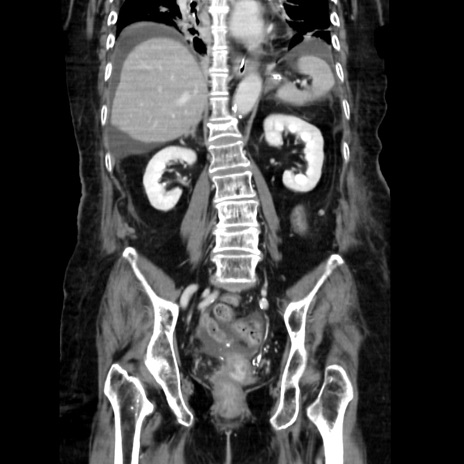

症例40(冠状断像)

【症例】90歳代女性

【主訴】腹痛・嘔吐

【現病歴】 食欲低下、嘔吐があり昨日他院受診。肺炎と診断され入院となる。入院後より腹部全体に圧痛あり。胃管留置され経過みていたが、症状持続するため、

当院転院となる。

【既往歴】胸椎圧迫骨折、胆石症

【身体所見】腹部:中央に激痛あり、圧痛あり、反跳痛不明

【データ】WBC 17100、CRP 18.82

冠状断像